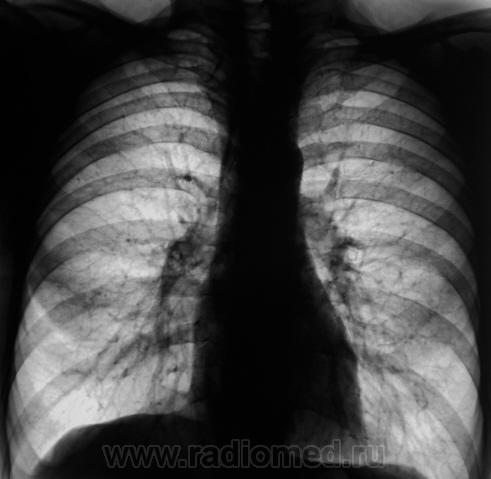

Еще контроль через 1 месяц.

Распад был изначально, но, к счастью больного, все закончилось практическим выздоровлением.

Долго что-то пневмонию лечили. А распад очень сомнительный. Больше на игру теней похож.